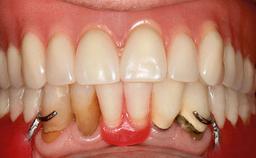

A 93-year-old female patient presented in September 2010 with an enlarged swelling on the lingual side of her lower incisors. At the time, she was essentially healthy, except for reduced vision due to bilateral age-related macular degeneration. She had been a heavy smoker (about 30 cigarettes a day) for the past 20 years after becoming a widow. The patient lived at home by herself, with full-time domestic support. An extraoral examination revealed nothing adverse. Intraoral plaque control was anything but ideal, and a soft-tissue tumescence was visible around the lingual aspect of 41–42. Because the nature of the lesion was not clear, a biopsy was carried out that revealed the inflammatory nature of the lesion. The panoramic radiograph showed six irregularly distributed mandibular implants supporting a full-arch prosthesis, with various degrees of interproximal peri-implant resorption. The periapical radiograph revealed interproximal bone resorption mesially and distally to implant 41.